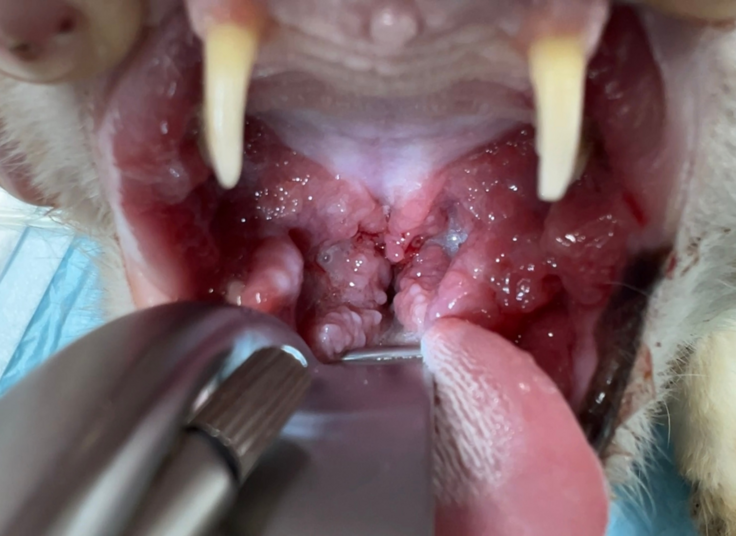

【処置後の写真:臼歯抜歯後、縫合処置をしました】

ご支援で導入した設備を使って、安全かつ短時間で全臼歯の抜歯を実施。術後はやわらかいごはんをしっかり食べられるようになり、今では穏やかな表情で日向ぼっこを楽しんでいます。

この他にも歯周病の猫さんの一部には、尾側口内炎と呼ばれる難治性の口内炎を患ってしまうことがあります。この場合、全臼歯抜歯に加えてレーザーによる炎症のコントロールも必要になります。口の中で食べ物がぶつかって痛いという苦痛に加えて、のど(咽頭部)にも痛みが出るため、食べることを拒絶したり、その痛みのせいで性格がきつくなってしまう子もいます。

【重度尾側口内炎によりのどに強い炎症がある猫さん】